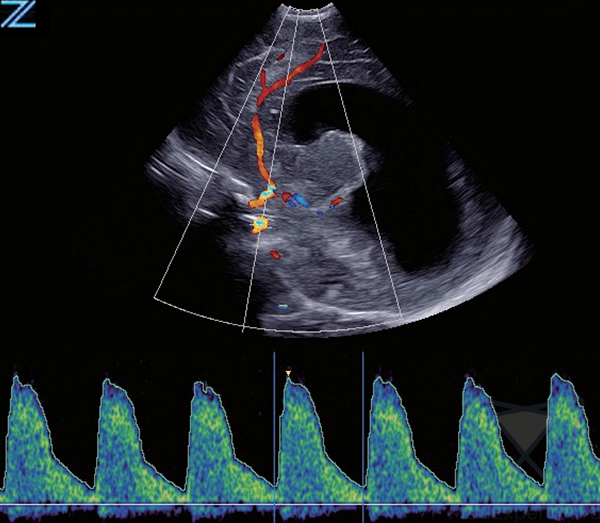

Система Zonare ZS3 оснащена инновационной программной технологией ZONE Sonography Technology (ZST), обеспечивающей диагностические преимущества в любых клинических ситуациях. Сфокусированное по всей глубине сканирования, четкое и детализированное изображение в В-режиме в сочетании с визуализацией в доплеровском режиме, позволяют охватить весь спектр клинических потребностей. УЗИ аппарат премиум класса подходит для проведения качественных исследований в любых условиях, благодаря быстрому переключению режимов и эргономичной, легкой портативной конструкции.

- Триплексный режим, с возможностью сохранения и просмотра кинопетли,

- Постоянно-волновой доплер с поддержкой на различных типах датчиках,